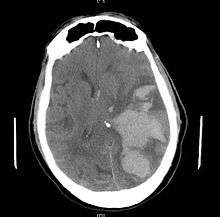

Treatment involves removal of the etiologic mass and decompressive craniectomy. Brain herniation can cause severe disability or death. In fact, when herniation is visible on a CT scan, the prognosis for a meaningful recovery of neurological function is poor.[2] The patient may become paralyzed on the same side as the lesion causing the pressure, or damage to parts of the brain caused by herniation may cause paralysis on the side opposite the lesion.[8] Damage to the midbrain, which contains the reticular activating network which regulates consciousness, will result in coma.[8] Damage to the cardio-respiratory centers in the medulla oblongata will cause respiratory arrest and (secondarily) cardiac arrest.[8] Current investigation is underway regarding the use of neuroprotective agents during the prolonged post-traumatic period of brain hypersensitivity associated with the syndrome.